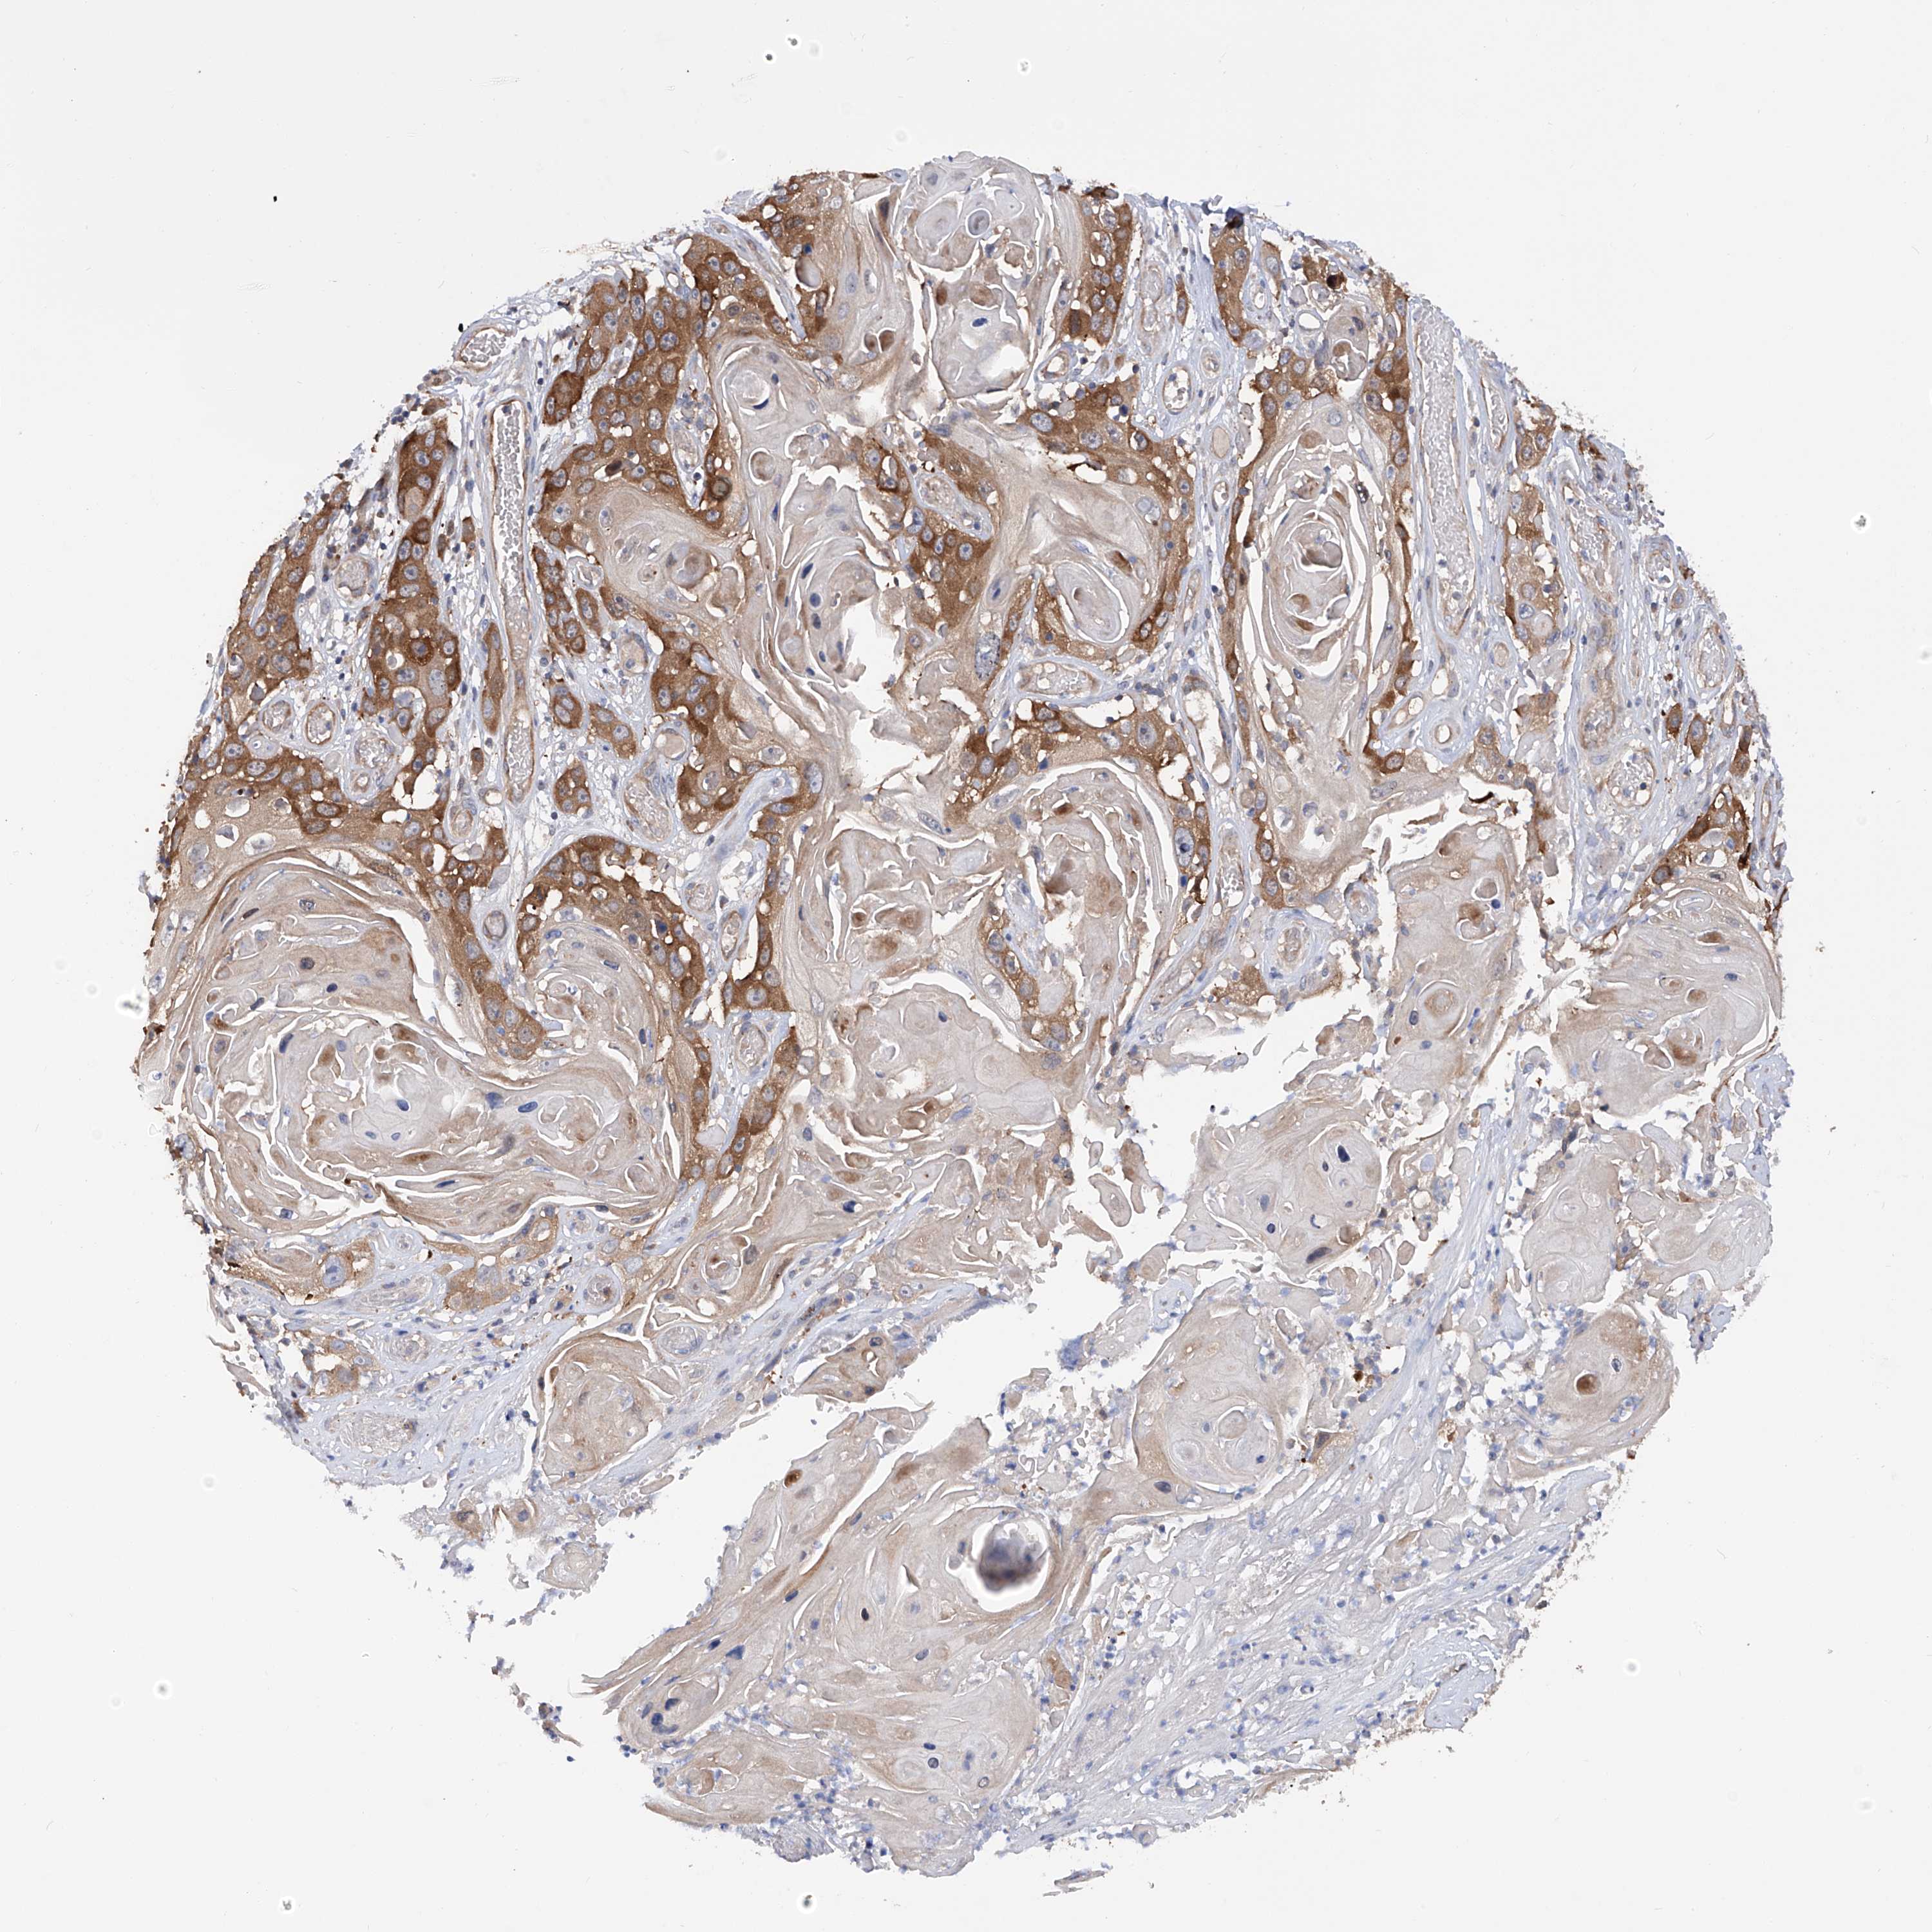

Basal cell and squamous cell cancer

SKIN CANCER - Protein expressioni

A mouse-over function shows sample information and annotation data. Click on an image to view it in a full screen mode. Samples can be filtered based on level of antibody staining by selecting one or several of the following categories: high, medium, low and not detected. The assay and annotation is described here.

Antibody stainingi

Antibody staining in the annotated cell types in the current human tissue is reported as not detected, low, medium, or high, based on conventional immunohistochemistry profiling in selected tissues. This score is based on the combination of the staining intensity and fraction of stained cells.

Each image is clickable and will lead to virtual microscopy that enables deeper exploration of all samples and also displays staining intensity scores, fraction scores and subcellular localization as well as patient and tissue information for each sample.

Antibody HPA030145

Staining

High

Medium

Low

Not detected

Intensity

Strong

Moderate

Weak

Negative

Quantity

>75%

75%-25%

<25%

None

Location

Nuclear

Cytoplasmic/membranous

Cytoplasmic/membranous,nuclear

Basal cell carcinoma